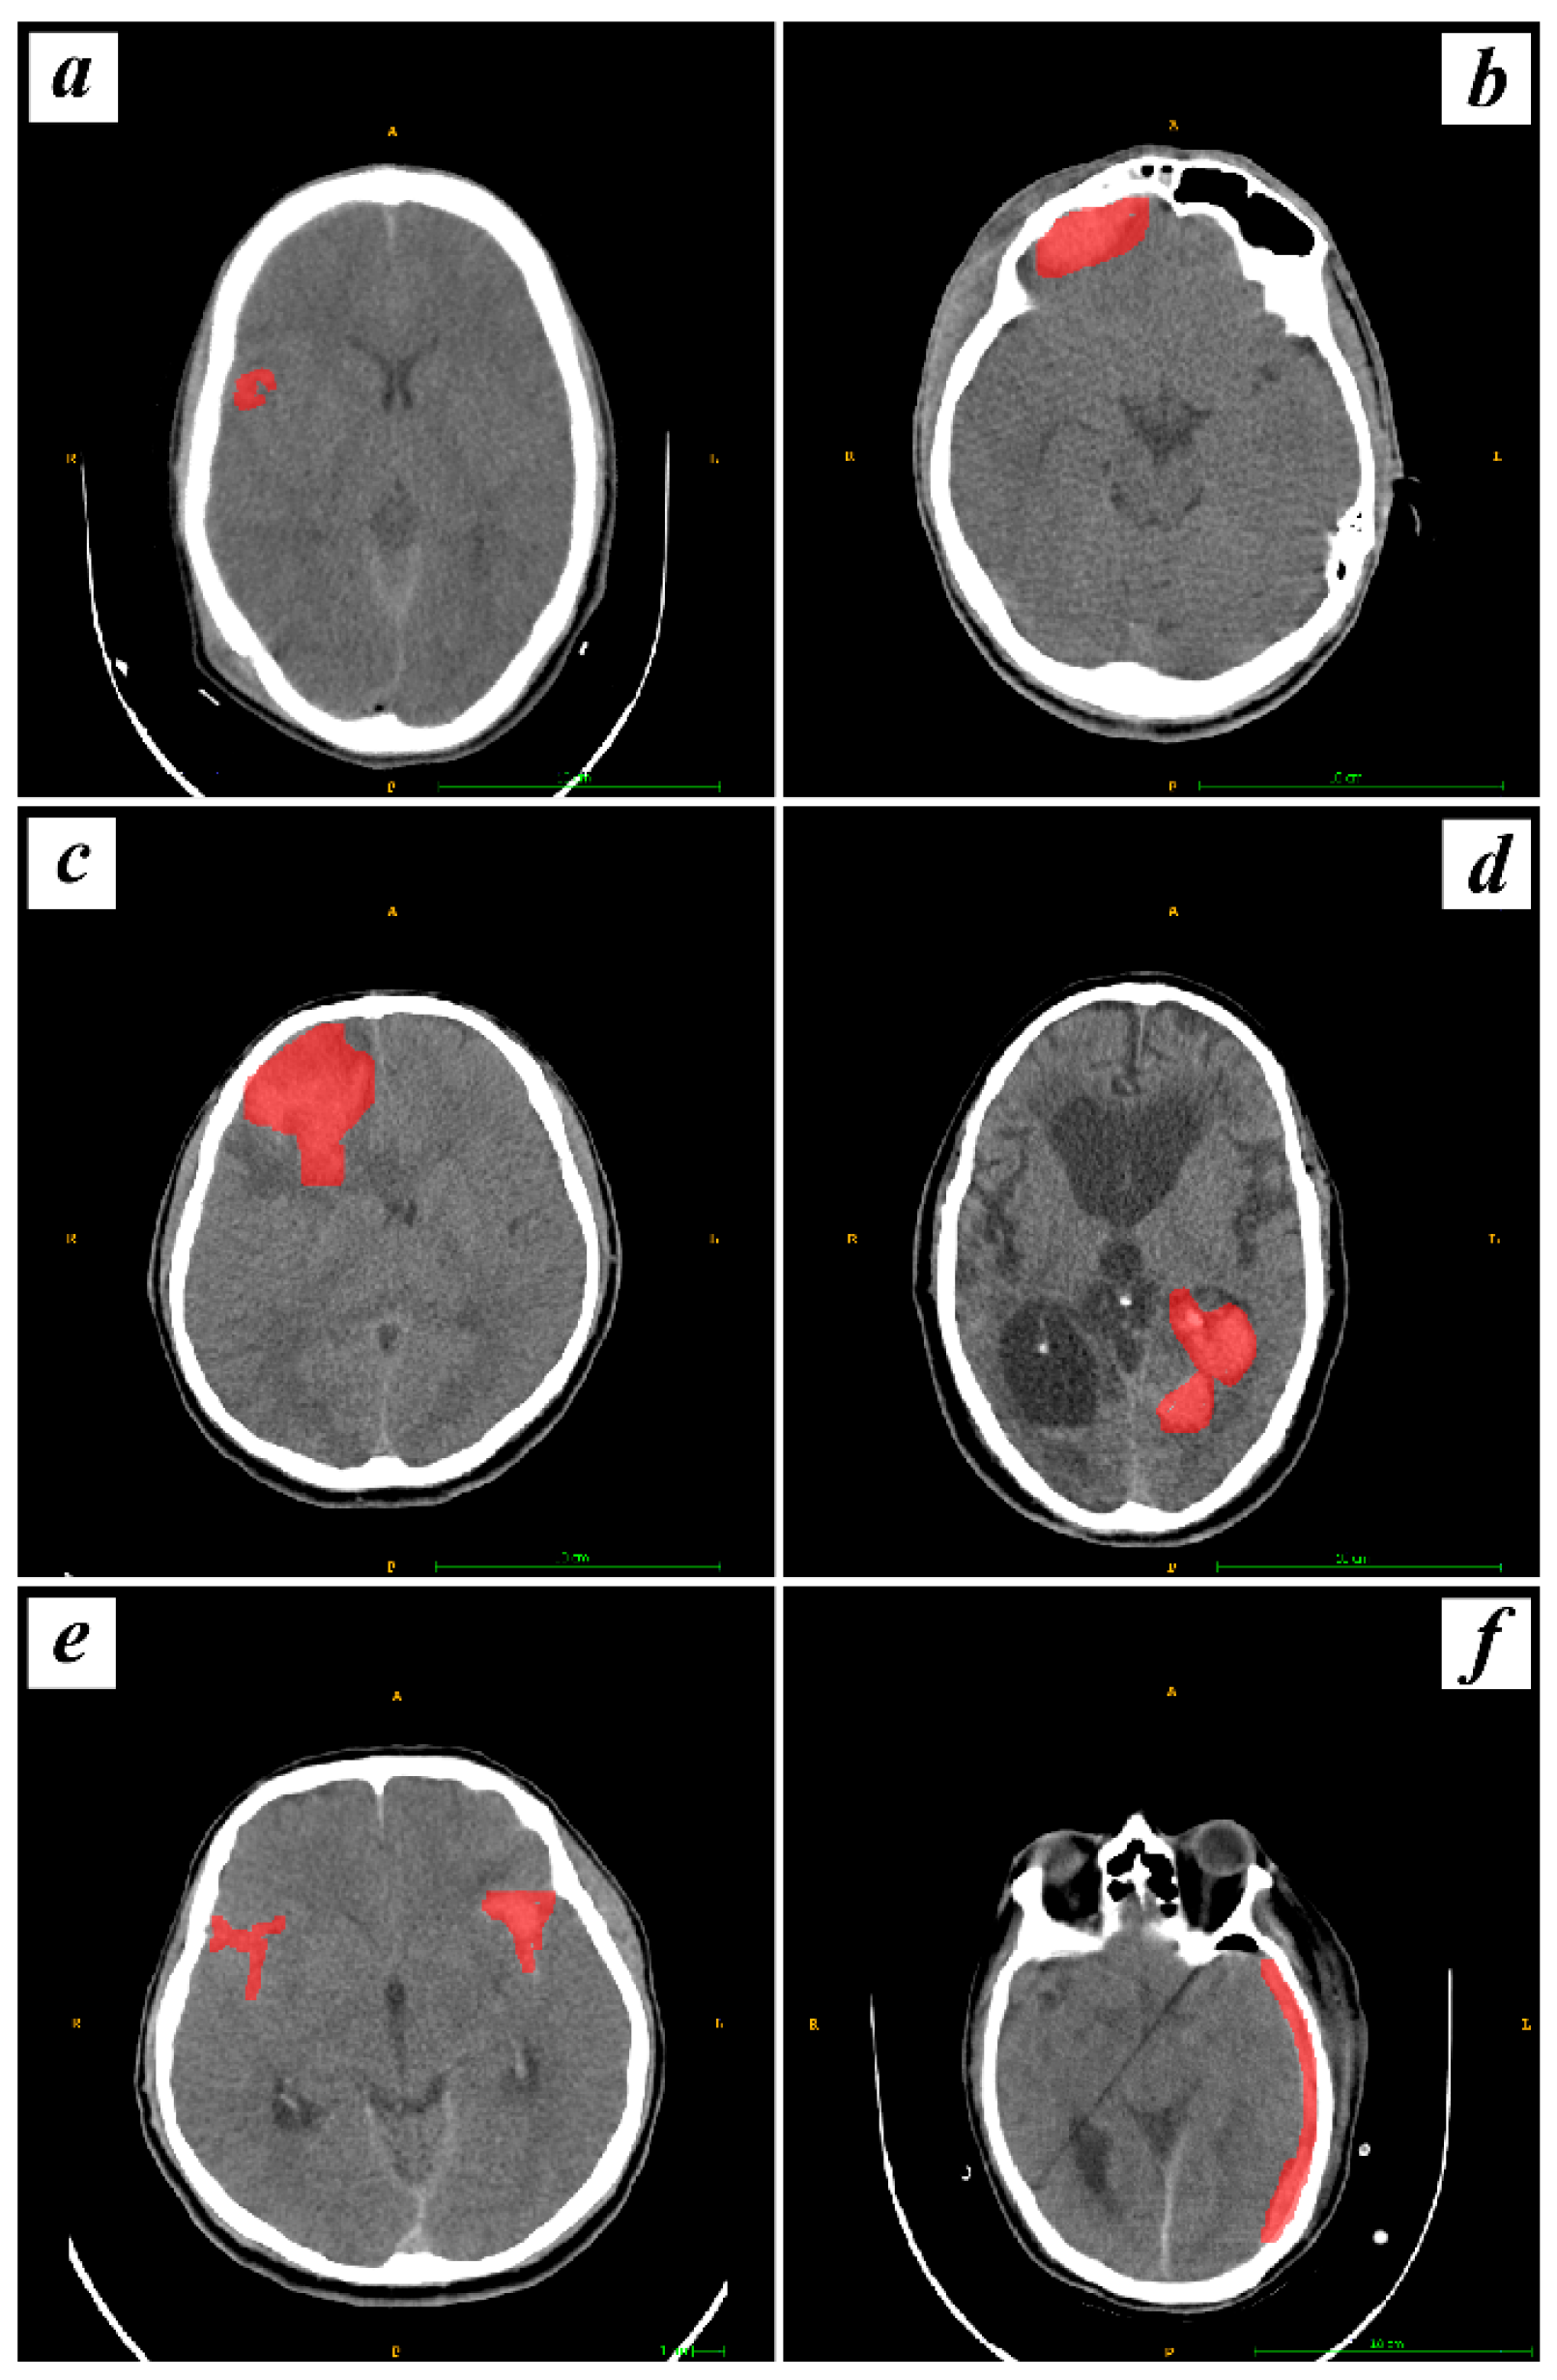

2.2. Segmentation of Intracranial Hemorrhage

3.1. Demographic Characteristics and Imaging Finding